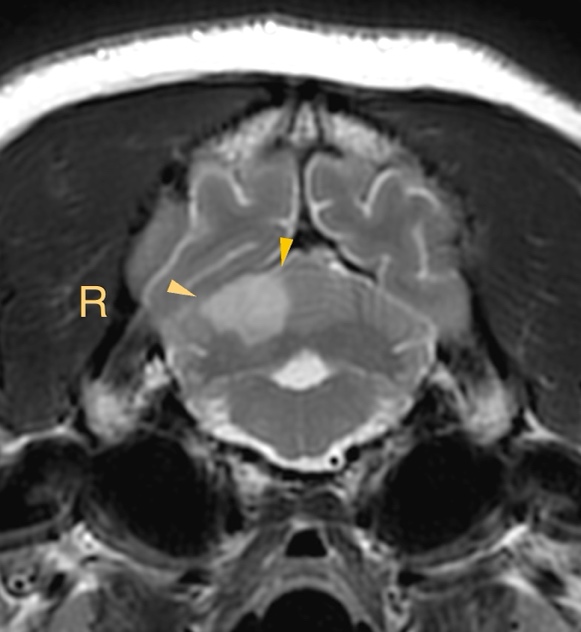

MRI所見

小脳右前小脳動脈領域にT2WI/FLAIR:高信号、DWI:高信号、ADC:一部低信号(部分的な拡散抑制を示唆)

→急性期小脳梗塞を強く疑う所見

この症例もやっぱり小脳中位核を含んでいます、瞳孔不同(右眼散瞳)があったに違いない!!

【MR画像】横断像 T2強調画像

【MR画像】横断像 T2強調画像